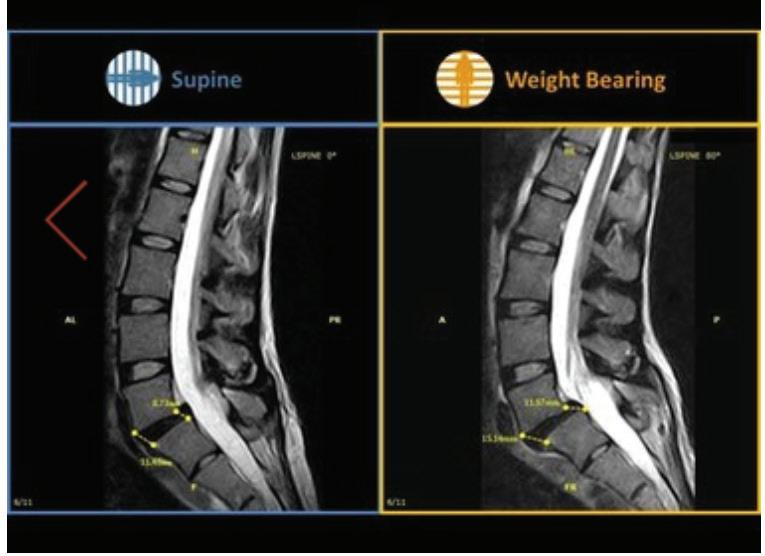

What a weight-bearing MRI reveals vs. a Supine MRI

G-scan Brio Reveals What Supine MRI Misses

Conventional MRI may not demonstrate the pathology related to these symptoms, but G-scan Brio gives you a new point of view so you can accurately diagnose MSK pathologies affected by weight-bearing position.

The G-scan Bro is superior to other MRIs because both the magnet and patient can rotate from 0 to 90 degrees.

G-scan Brio offers a revolutionary MRI approach that increases diagnostic accuracy and confidence for musculoskeletal applications.

G-Scan - Anterolistesis G-Scan - Disc Modification Cervical scan

Supine MRI G-Scan - Anterolistesis G-Scan - Disc Modification Cervical scan More Detail, Better Accuracy,